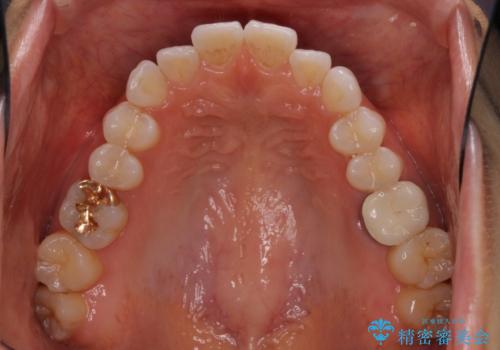

- 前歯のデコボコと上下スペースと前歯の隙間を気にして来院された患者様です。

目立たない装置を希望とのことでインビザラインにより、デコボコを解消しつつ、上下の前歯の隙間を閉じていくこととしました。

デコボコはあっという間に解消されましたが、上下前歯の隙間がなかなか解消されませんでした。

飲み込みの際に舌を前方に突出する癖があり、飲み込みの度に前歯に強く接触していたため、上下前歯の隙間が維持されていました。

舌の訓練を徹底していただいたことで、徐々に隙間は解消され、きれいな歯列に整えることができました。